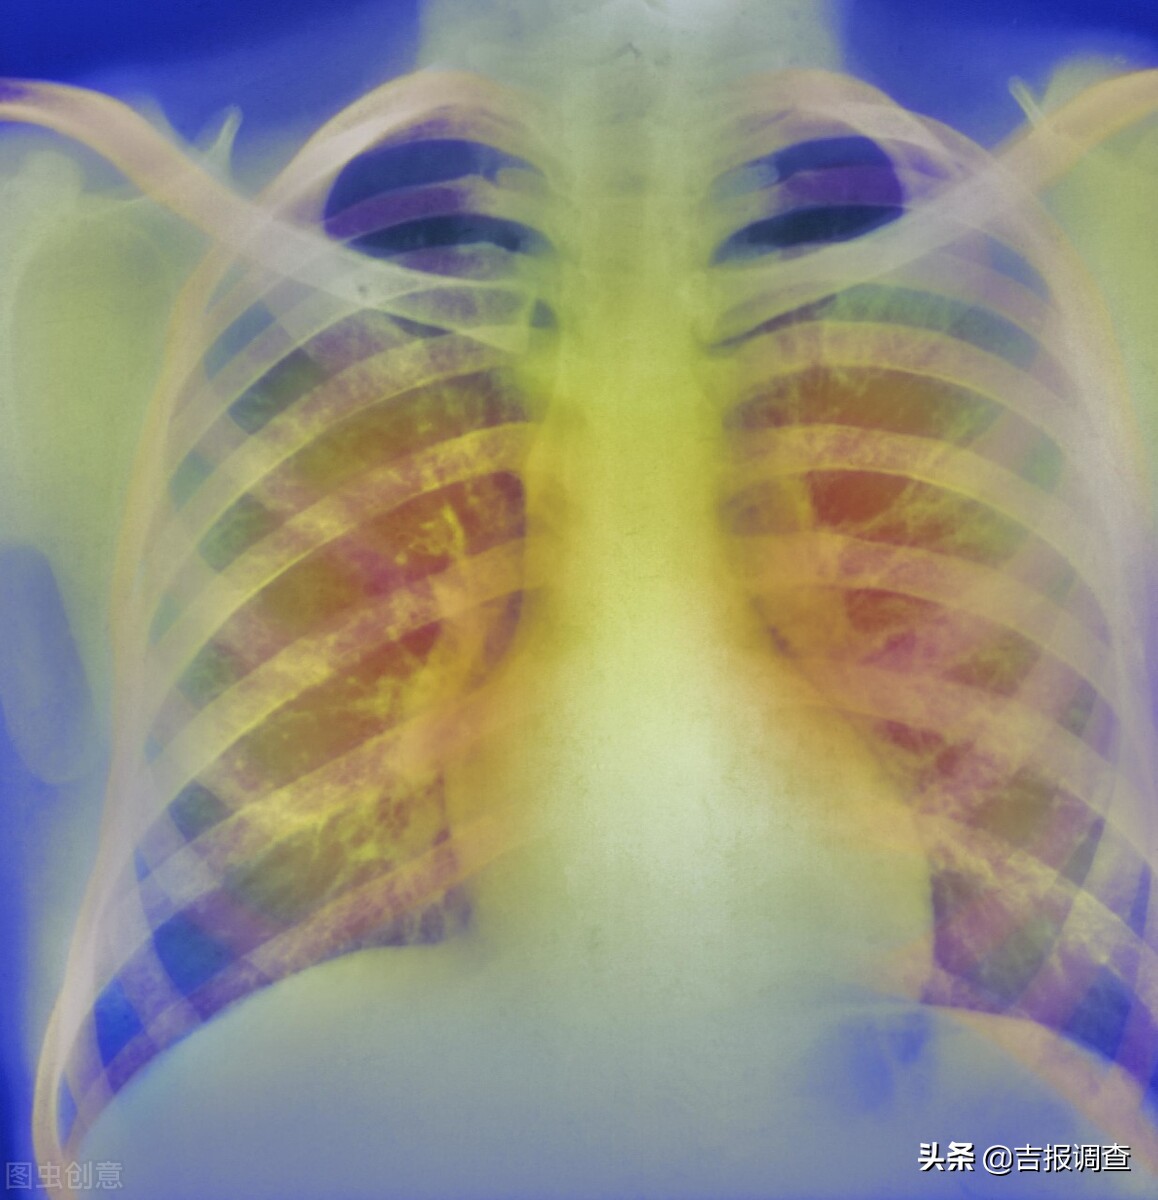

夏天来了,北京弘医堂中医专家给慢性肺病患者提个醒:慢性肺病好发于冬季,到了夏季,咳、喘、呼吸受限、活动困难等状况均有所缓解,很多患者会因此放松对疾病的关注和治疗。其实夏季是肺部慢性疾病康复的最佳季节,针对肺气肿、慢支炎、慢性阻塞性肺炎、间质性肺病等肺病患者来说,尤为重要。

慢性肺病大多病程较长,病情复杂。慢性支气管炎、慢阻肺、支气管哮喘、肺源性心脏病等疾病,多是由肺系急性病变未及时适当治疗,或原本体质虚弱,反复感染外邪迁延发展而致。夏季气温升高,人体血液循环较好,慢支炎、肺气肿、支气管哮喘等病症表现往往不明显,致使许多患者产生疾病好转的错觉,从而放松警惕,如不及时治疗,常常会失去治疗的最好机会,此时如果忽视对疾病的巩固治疗,针对各类慢性肺病患者来说,是极其不利的。